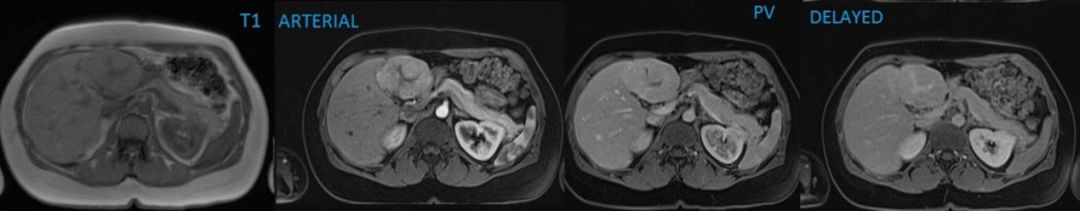

MR:T1WI 等、T2WI 等或略高信号,边缘模糊;中央瘢痕 T2WI 高信号;动脉期明显强化,快进慢出、快进同出、快进快出;门脉期通常较周围肝实质信号等或略低,也可略高;延迟期中央瘢痕逐渐强化;肝胆期通常为不均匀高/等信号;T2WI 边缘模糊,增强扫描边界清楚

MR 肝胆期:由于纤维瘢痕含量不同,肝胆期可表现为不均匀高/等信号(53.3%,),不均匀低信号(16.7%),均匀高/等信号(23%),均匀低信号(6.7%)。